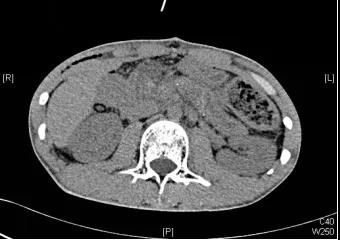

所幸,历经约7个小时的努力,医生们顺利闯过手术禁区,术中仅出血约100ml。术后,小黄恢复良好,第八天顺利出院,目前进一步随访,他的情况也很良好。

(术后CT图)